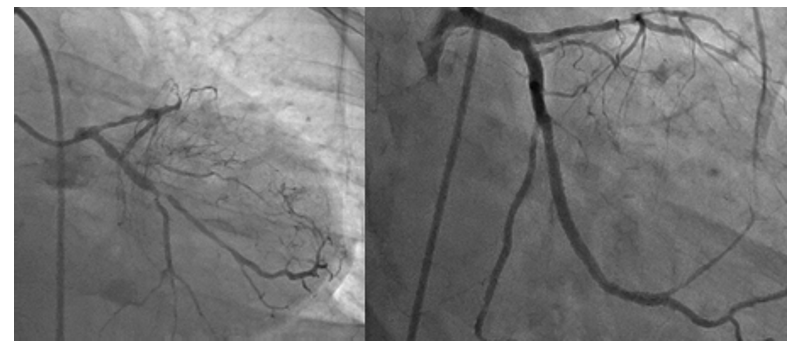

one case of HCR was described this patient presented with acute AWMI coronary anatomy showed osteal LAD with short left main underwent LIMA to LAD and long lesion with 99% RCA EF 40% procedure was uncomplicated hospital stay was 8 days Pic of HRS (123).

Figure 2: Pre and Post PCI OF RCA

Figure 3: Pre and Post Staged PCI OF LCX